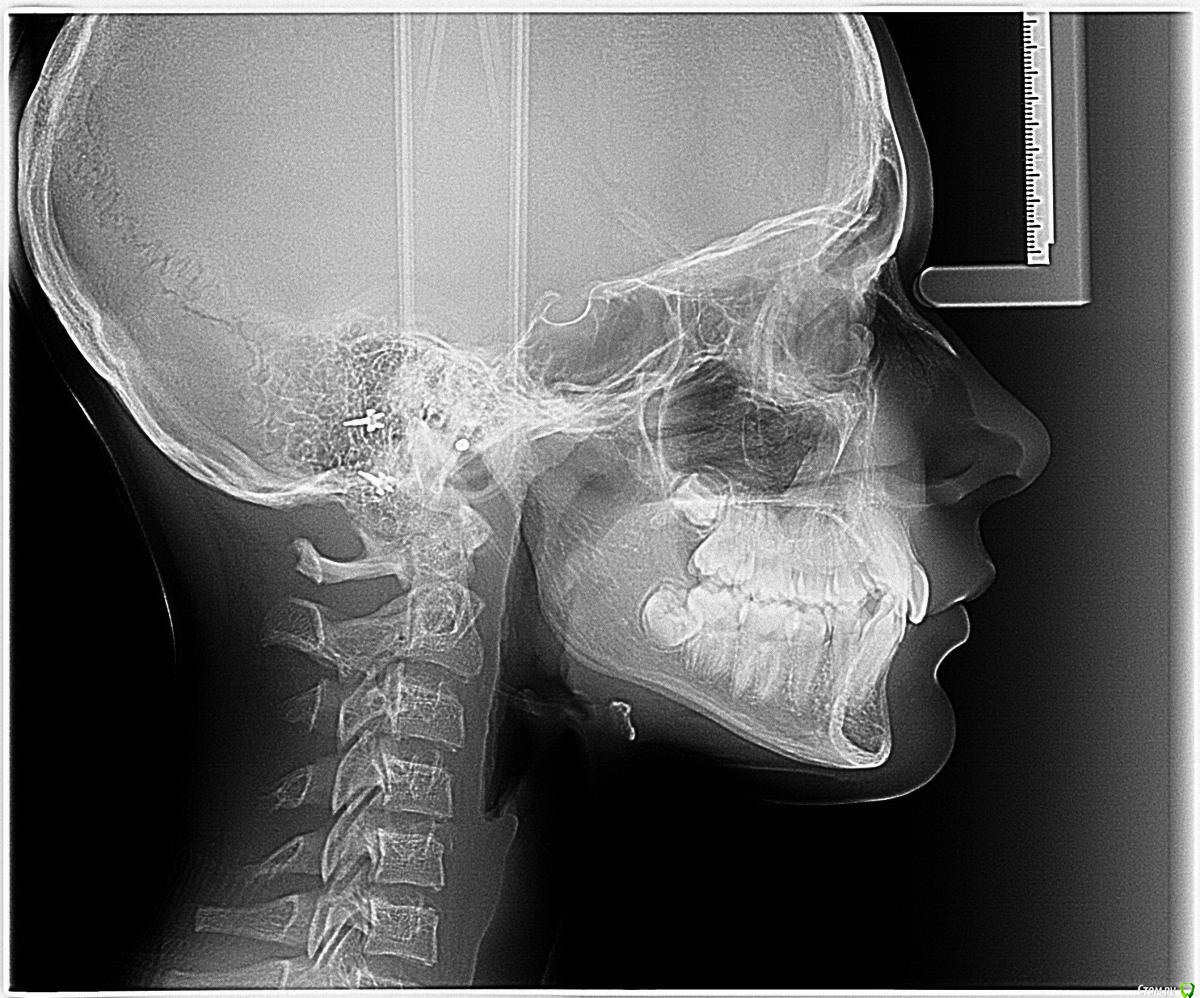

НОЛЬ Опубликовано 9 февраля, 2020 Поделиться Опубликовано 9 февраля, 2020 Прошу совета у специалистов!!! Мнения докторов у которых были на консультации неоднозначны. ВОПРОС: Возможно ли исправить ситуацию посредством скоб или брекетов.. или надо удалять..??? Возраст девочки 13 лет. Ссылка на комментарий